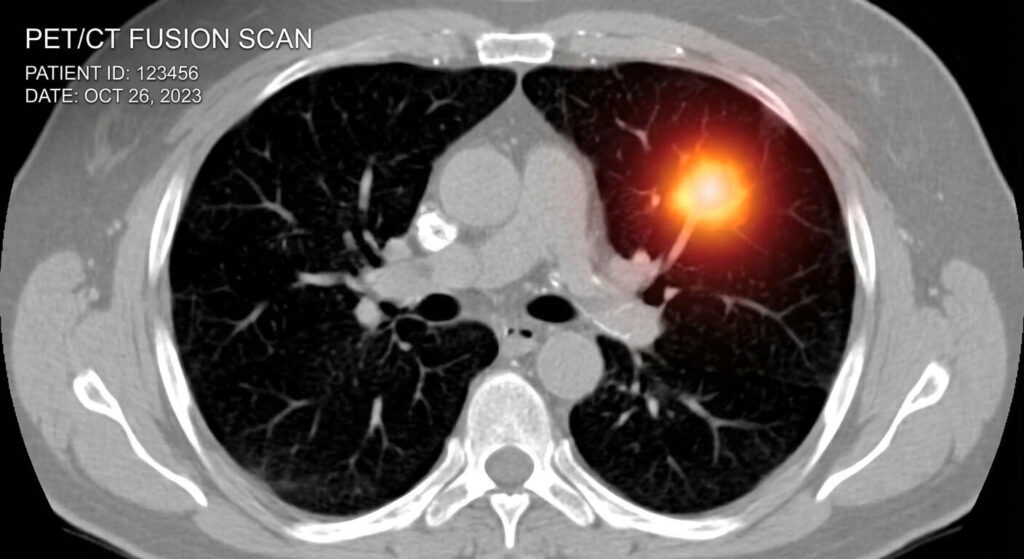

Une fois injecté, ce « sucre marqué » circule dans le sang. Les zones de forte activité métabolique vont capter ce traceur de manière préférentielle. Lors de l’acquisition des images, la machine détecte les radiations émises par le FDG accumulé, créant des taches lumineuses sur l’écran. Un foyer hypermétabolique est donc, littéralement, une zone qui « s’allume » parce qu’elle consomme du sucre de façon frénétique.

| Poumon | Nodule tumoral ou infection. | Inflammation globale (tabac, pollution). |